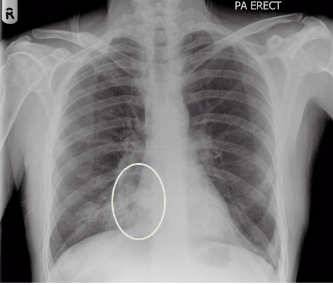

whats wrong here?

whitening of the lung - in the right middle zone of the lung